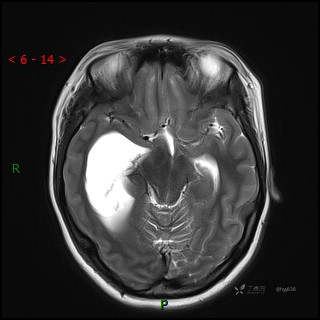

MRI平扫

CE